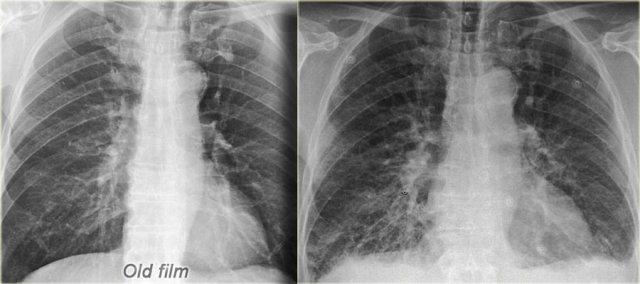

Phim cũ để so sánh (trái) Suy tim sung huyết với tái phân phối tuần hoàn, phù mô kẽ và một ít dịch màng phổi

Chỉ số tim-ngực (CTR) là tỷ lệ giữa đường kính ngang của tim so với đường kính trong của lồng ngực tại điểm rộng nhất ngay phía trên vòm hoành, được đo trên phim X-quang ngực tư thế thẳng (PA).

Hình bên trái là bệnh nhân suy tim sung huyết.

Kích thước tim tăng so với phim cũ.

Các dấu hiệu khác của suy tim sung huyết cũng hiện diện, bao gồm tái phân phối tuần hoàn phổi, phù mô kẽ và một ít dịch màng phổi.

Trên phim chụp tư thế nằm ngửa, bóng tim sẽ lớn hơn do hiệu ứng phóng đại và vị trí cao của các vòm hoành.

Các phép đo chính xác không thực sự hữu ích trong trường hợp này, nhưng việc so sánh với các phim chụp tư thế nằm ngửa cũ có thể có giá trị.